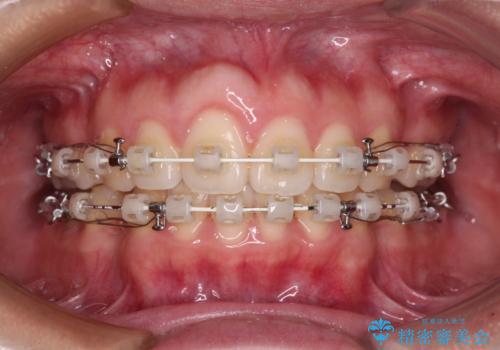

- 矯正装置

- 審美装置

- 1年8ヶ月

- 10-30回